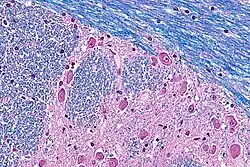

In pure LFB stains, myelin fibers appear blue, with areas of the highest concentration of myelin appearing darker. The blue stain appears on a white background.

Typically, cresyl violet is used as counterstain. Cresyl violet binds to Nissl substance, which is concentrated around a neural cell's nucleus; such a counterstain allows differentiation between myelenated axons, cell bodies, and unmyelenated axons or glial cells. In such a stain, myelin fibers appear blue, neuropil appears pink (or faint purple), and neuron cell bodies appear purple.